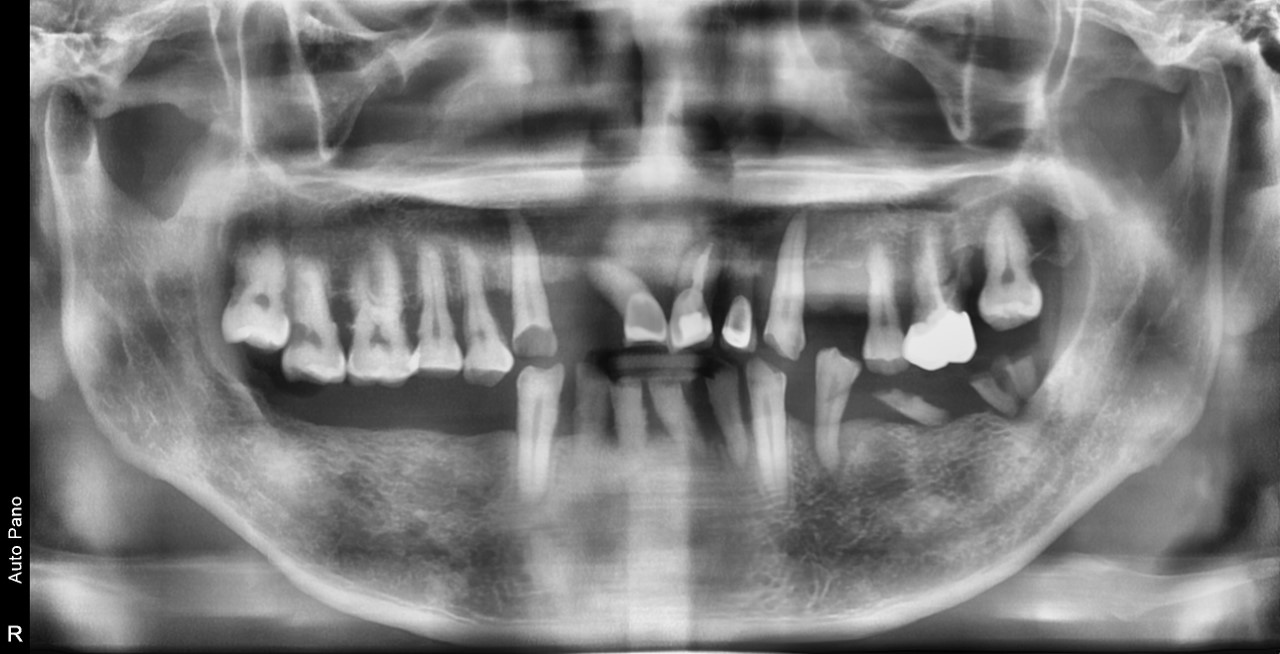

IMPLANT CASE BEFORE AND AFTER

임플란트 치료 전후

구강과 안모의 조화, 기능을 면밀하게 파악하여 1:1 맞춤 시술로 진행하는 안전하고 정확한 민치과의원의 임플란트 치료